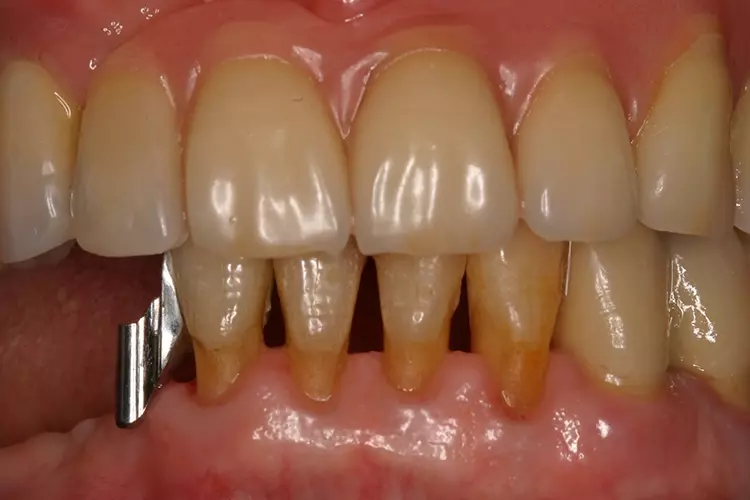

Als relative Kontraindikation sind karies- und restaurationsfreie Pfeilerzähne mit zervikalen keilförmigen Defekten über 1 mm Tiefe zu nennen, da diese zu einer erhöhten Frakturgefahr des Pfeilerzahnes bei Belastung führen. Adhäsivattachments können zur Reparatur vorhandener Doppelkronen- oder Geschiebearbeiten verwendet werden, sofern der verbliebene Nachbarzahn einer verloren gegangenen Doppelkrone karies- und restaurationsfrei ist. Die Matrize wird in diesem Fall in die ausgeschliffene Doppelkrone oder in die Geschiebekrone des verlorenen Pfeilerzahns eingeklebt (Abb. 1 bis 4).

Adhäsivattachments werden in der Regel aus Cobalt-Chrom(CoCr)-Legierungen hergestellt. Um eine ausreichende Steifigkeit des Materials zu gewährleisten, sollte eine Mindeststärke des Adhäsivflügels von 0,7 mm eingehalten werden. Die Ränder sollten möglichst auf Minimalstärke ausgearbeitet werden.

Die Klebefläche sollte mindestens 30 mm2 betragen. Empfohlen werden kostengünstige extrakoronale, semipräzise Stabgeschiebe mit auswechselbaren Kunststoffmatrizen (z.B. Preci-Vertix, Fa. Ceka, Hannover). Um Frakturen zu vermeiden, sollten die Geschiebestäbe extrakoronal mit einer Mindestverbinderhöhe von 3 mm zwischen Stabgeschiebe und Adhäsivflügel konstruiert werden. Die auf 3 mm kürzbaren Geschiebestäbe sollten parodontalfreundlich mit einer Führung für Interdentalraumbürstchen durch eine direkte, ponticförmige Auflage auf dem Kieferkamm angebracht werden.